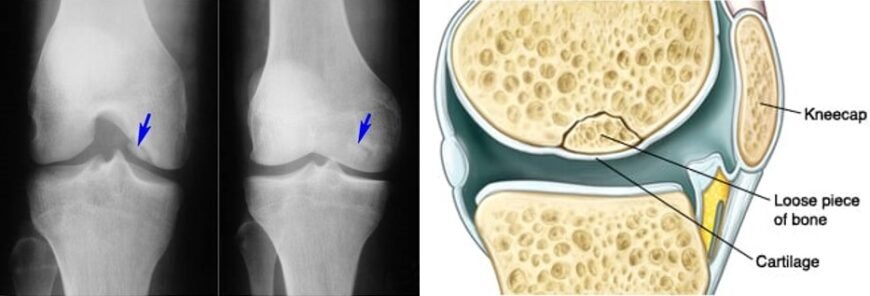

Почнемо з того, що хвороба Кеніга, більш відома науково як остеохондрит розсійка, являє собою стан, за якого частина кістки вкритої хрящем відшаровується — прямо всередині суглоба. Зазвичай ця біда коїться у коліні. Коли все отак тріщить, що може бути гірше?

- Рентген: заморозити кадр, щоб побачити те, що приховано.

- МРТ: глибокий скан мозку сутності кістки і хряща.